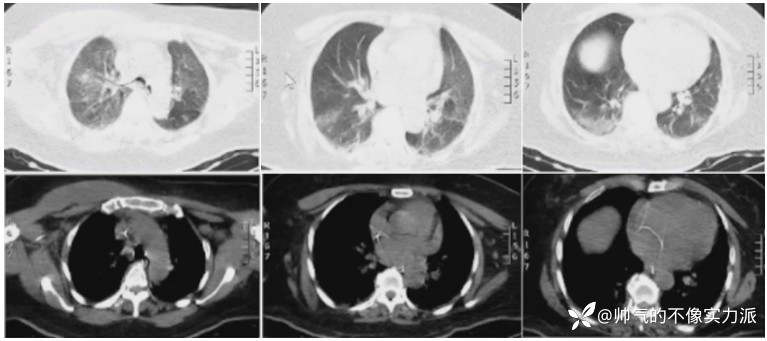

- 胸部CT(7月28日):双下肺渗出、实变,双侧胸膜下少许胸腔积液(图1)。

图1 患者入院后胸部CT

插管第2天(8月9日)复查胸部CT:右上肺实变较前明显加重,双侧胸腔积液较前明显增多(图3)。

图3 复查胸部CT(8月9日)